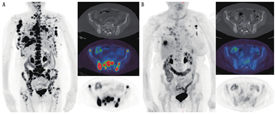

1.骨显像(包括SPECT和SPECT/CT)。用99Tcm标记的二膦酸盐进行骨显像始于20世纪70年代,这类显像剂在血液和软组织中清除速度快,注射后2 h即可采集到有良好对比度的图像[23]。尽管其数十年来被广泛用于检出和监测骨转移,但可供选择的现代影像技术具有更优的灵敏度和特异性[5,6,16,18]。然而,SPECT断层和SPECT/CT融合显像技术的出现,延长了骨显像的"寿命"。这些硬件和重建方法既提高了检测的灵敏度(更好的对比分辨率),又提高了检测的特异性(可显示与CT解剖相关的三维数据)[24,25]。结合CT形态学特征可提高骨显像的特异性,更准确描述放射性浓聚点的良恶性,增加对扫描结果解释准确性的信心,同时减少了模棱两可的结论(图1)[25]。